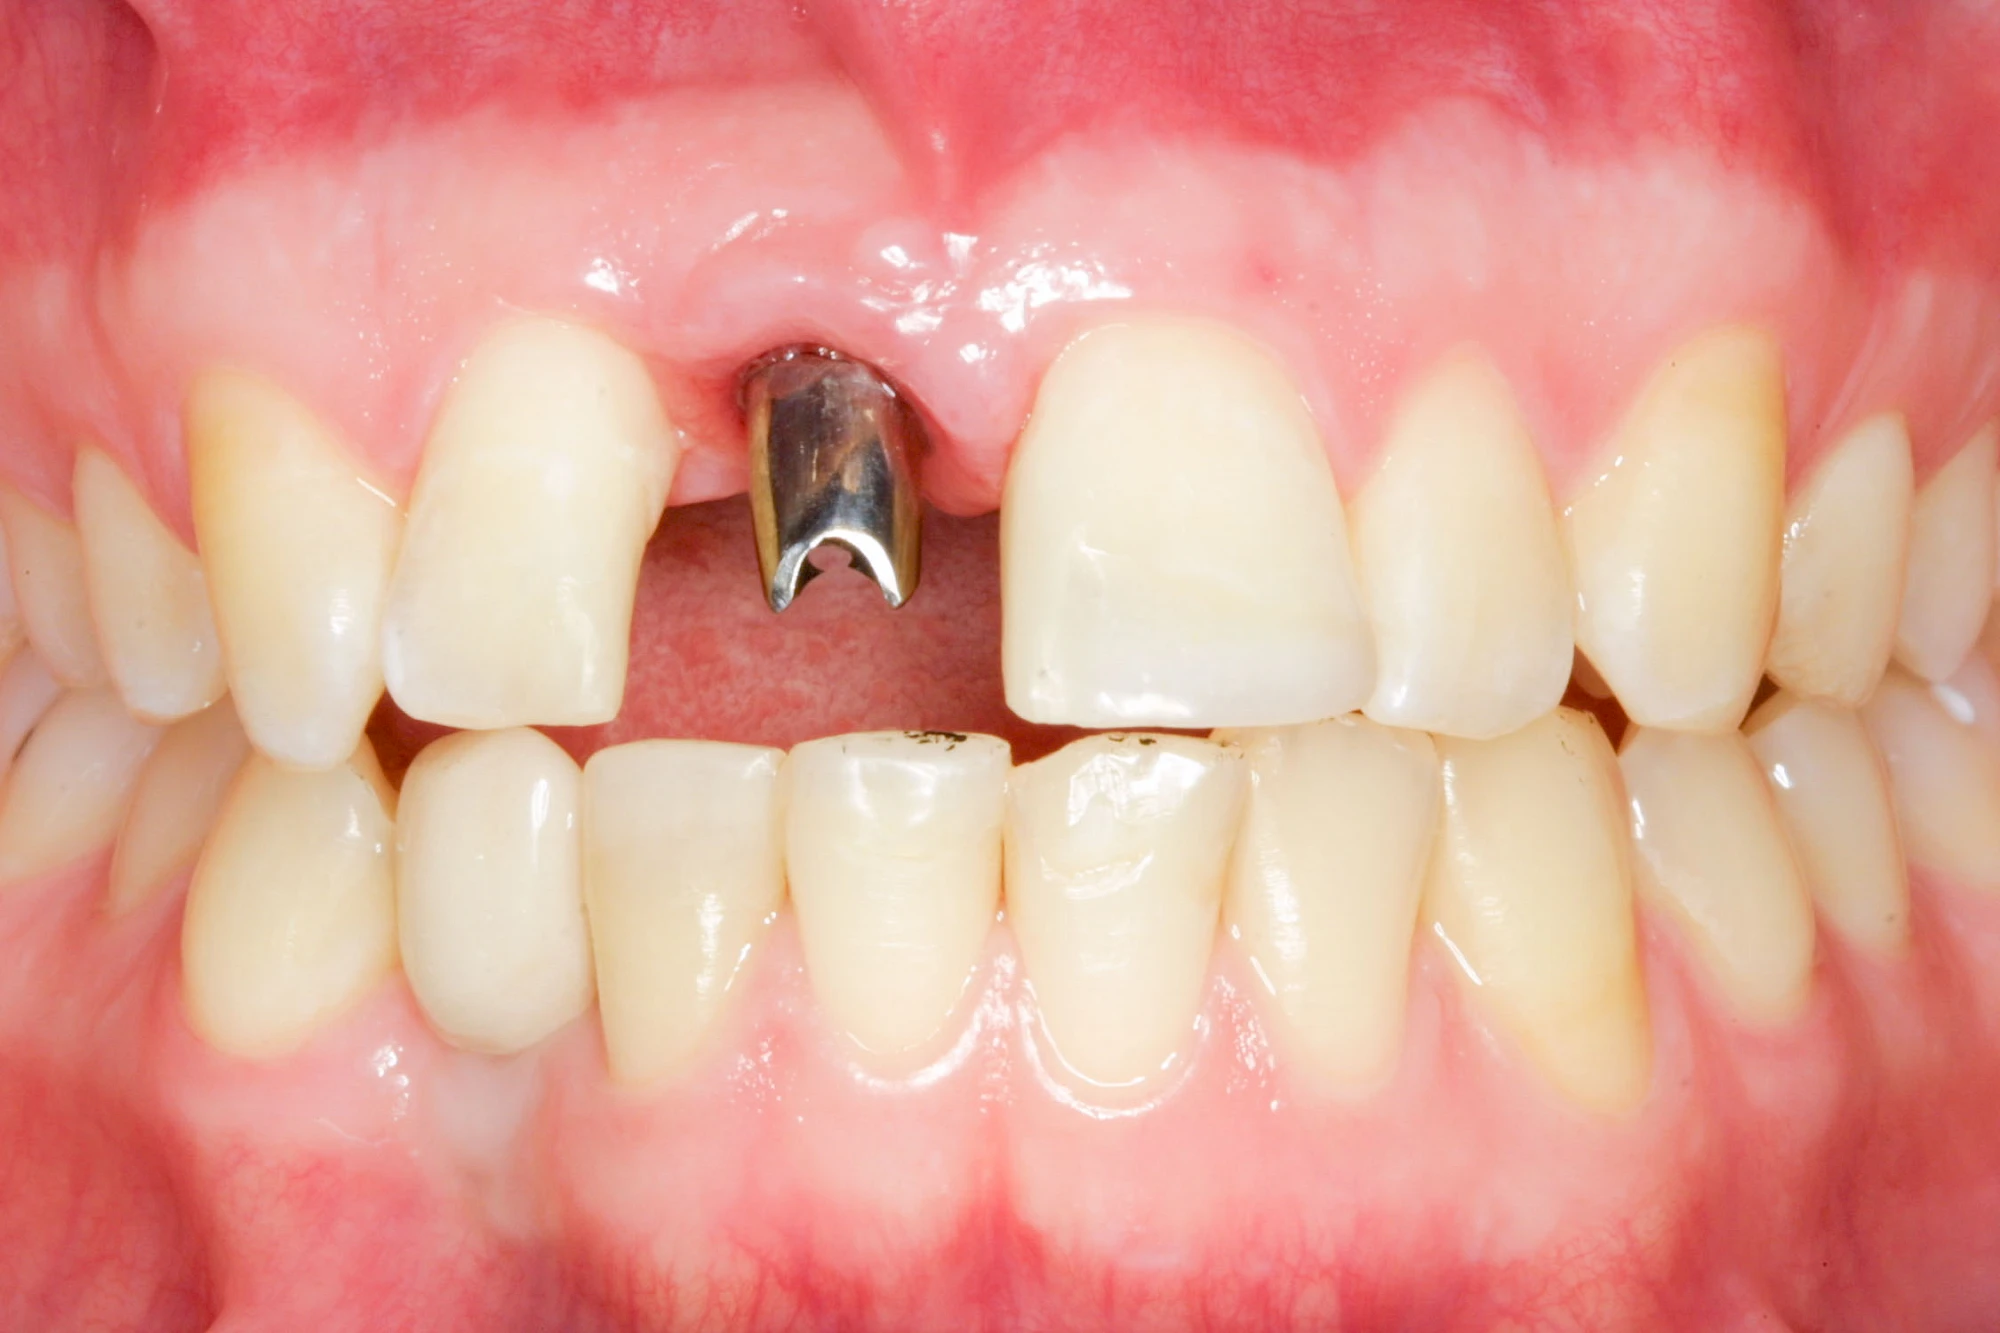

"Stiftzahn" und "Implantat" ist nicht dasselbe! Bei einem Stiftzahn wird die Zahnkrone mit einem Stift in die noch vorhandene eigene Zahnwurzel zementiert. Ein Implantat im Gegensatz dazu ist selbst die (künstliche) Zahnwurzel, die dann weiter mit einem Zahnersatz versorgt wird.

Implantate: Kronen & Brücken

Fehlen einzelne Zähne und die Nachbarzähne sind unbeschadet oder gut zahnärztlich versorgt, werden immer häufiger Implantate gewählt, um die Lücken zu schließen. Auch bei größeren oder verteilten Lücken, wenn keine herausnehmbare Prothese gewünscht ist, werden Implantate für Kronen- bzw. Brückenversorgungen gesetzt. In Einzelfällen entscheiden sich sogar zahnlose Patienten für eine festsitzende Versorgung auf Implantaten.

Varianten zur Verankerung von festsitzendem Zahnersatz auf Implantaten